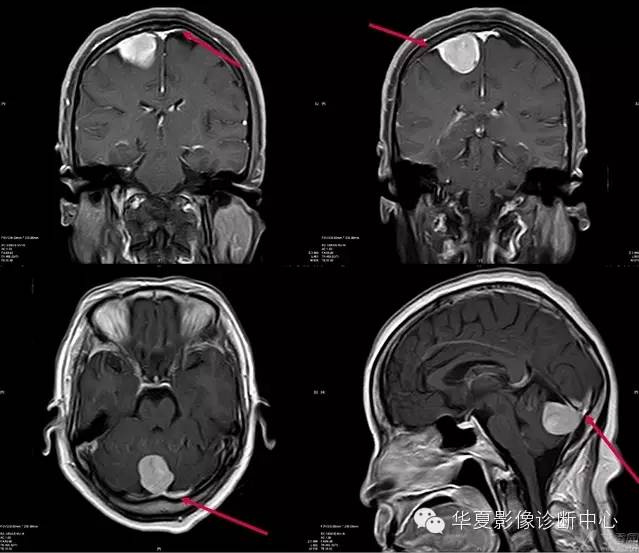

脑膜尾征

“在增强的MRI或CT图像上,表现为强化并增粗的硬脑膜从肿块延伸出来,长0.5~3cm,形似一条尾巴,称作脑膜尾征或脑膜征,也叫硬膜尾征。

硬脑膜尾征是脑膜瘤较常见的增强MRI表现,最初有人提出硬脑膜尾征是来源于肿瘤的直接侵犯,但后来许多研究显示硬脑膜尾很少或没有肿瘤的累及,也有人认为是硬脑膜的反应性改变。目前认为肿瘤侵犯和富血管反应双重机制是产生硬脑膜尾征的原因。脑膜瘤为颅内常见肿瘤,肿瘤起病慢,病程长。典型脑膜瘤多为圆形或类圆形,少数为不规则形,边界清楚锐利。CT平扫大部分表现为均匀高密度15%~20%含钙化,甚至有的完全钙化。25%~30%表现为等密度,常因占位效应或病灶周围水肿而发现。少部分脑膜瘤表现为低密度,多为肿瘤的囊变、坏死所致,少数为胶原纤维化、陈旧性出血或较多的脂肪沉积所致;约10%的脑膜瘤为混合密度,常见瘤周水肿。CT增强扫描除钙化较明显的砂粒型脑膜瘤可能不增强或增强较少外,肿瘤的实质部分往往呈较明显的均匀增强化。 大多数脑膜瘤MRI表现为1WI呈稍低或等信号,T2WI呈稍高或等信号。脑膜瘤内部信号常不均匀,表现为颗粒状、斑点状,这些与肿瘤内血管、钙化、囊变和砂粒体及肿瘤内纤维分隔有关。增强扫描时,脑膜瘤立即发生显著增强并有延迟强化,持续时间达30~60分钟。 确定有没有硬脑膜尾征有3个标准: